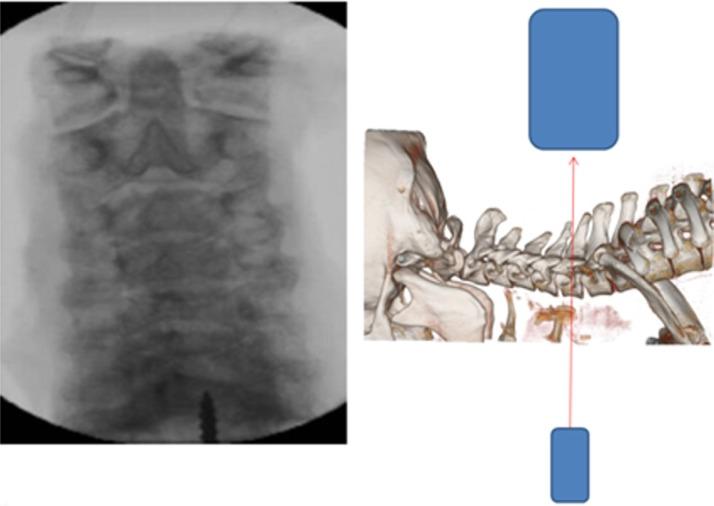

方法

利用先前确定的关节突形态测量法来确定下颈椎经关节突螺钉置入的理想轨迹。开发了一种独特的瞄准导向器,以允许在无侧位透视荧光镜检查引导的情况下将克氏针以90°穿过关节突关节。在7个尸体标本中经皮放置克氏针和空心螺钉。器械置入完全在改良前后位透视荧光镜检查下进行。由2名接受过专科培训的骨科脊柱外科医生使用计算机断层扫描对所有标本的螺钉置入情况进行评估,以确定是否可接受。通过开放解剖来确认影像学解释。可接受的置入定义为螺钉穿过关节突关节,在下关节突和上关节突获得锚定,且不侵犯关键结构。位置不当定义为侵犯横突孔、椎管或神经根或固定不充分。